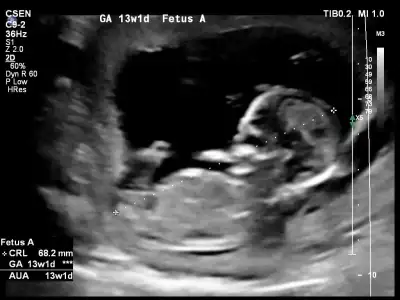

Merhaba Ikra meyra Ikra meyra canım, bir tahmin alabilir miyim ben de 13+2 olduk. :KK36:

Eklentiler

• 20201021_114201.webp

20201021_114201.webp

23,3 KB · Görüntüleme: 63

• 20201021_114209.webp

20201021_114209.webp

23,7 KB · Görüntüleme: 51

• 20201021_114216.webp

20201021_114216.webp

18,4 KB · Görüntüleme: 80